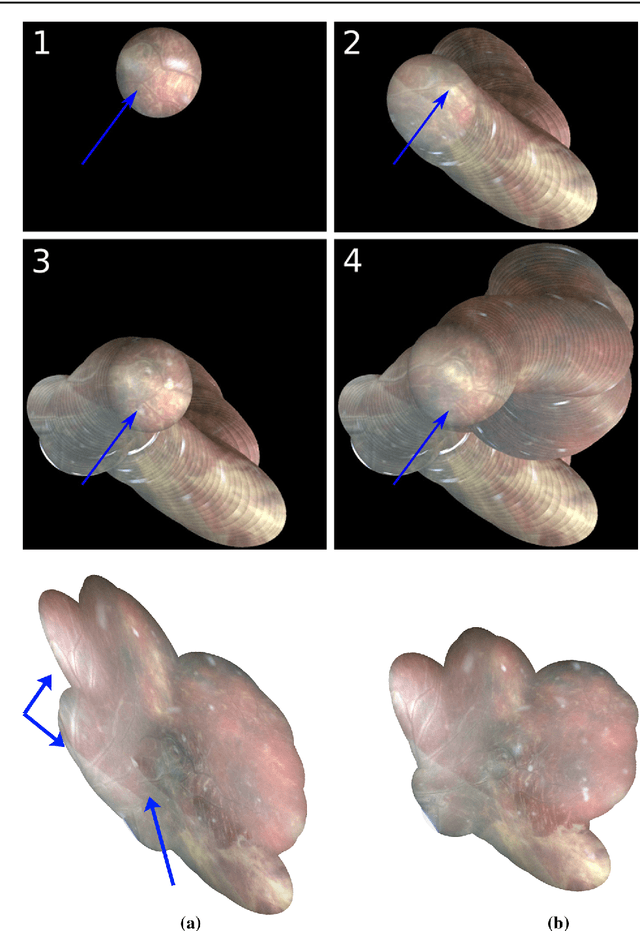

Purpose: The standard clinical treatment of Twin-to-Twin Transfusion Syndrome consists in the photo-coagulation of undesired anastomoses located on the placenta which are responsible to a blood transfer between the two twins. While being the standard of care procedure, fetoscopy suffers from a limited field-of-view of the placenta resulting in missed anastomoses. To facilitate the task of the clinician, building a global map of the placenta providing a larger overview of the vascular network is highly desired. Methods: To overcome the challenging visual conditions inherent to in vivo sequences (low contrast, obstructions or presence of artifacts, among others), we propose the following contributions: (i) robust pairwise registration is achieved by aligning the orientation of the image gradients, and (ii) difficulties regarding long-range consistency (e.g. due to the presence of outliers) is tackled via a bag-of-word strategy, which identifies overlapping frames of the sequence to be registered regardless of their respective location in time. Results: In addition to visual difficulties, in vivo sequences are characterised by the intrinsic absence of gold standard. We present mosaics motivating qualitatively our methodological choices and demonstrating their promising aspect. We also demonstrate semi-quantitatively, via visual inspection of registration results, the efficacy of our registration approach in comparison to two standard baselines. Conclusion: This paper proposes the first approach for the construction of mosaics of placenta in in vivo fetoscopy sequences. Robustness to visual challenges during registration and long-range temporal consistency are proposed, offering first positive results on in vivo data for which standard mosaicking techniques are not applicable.